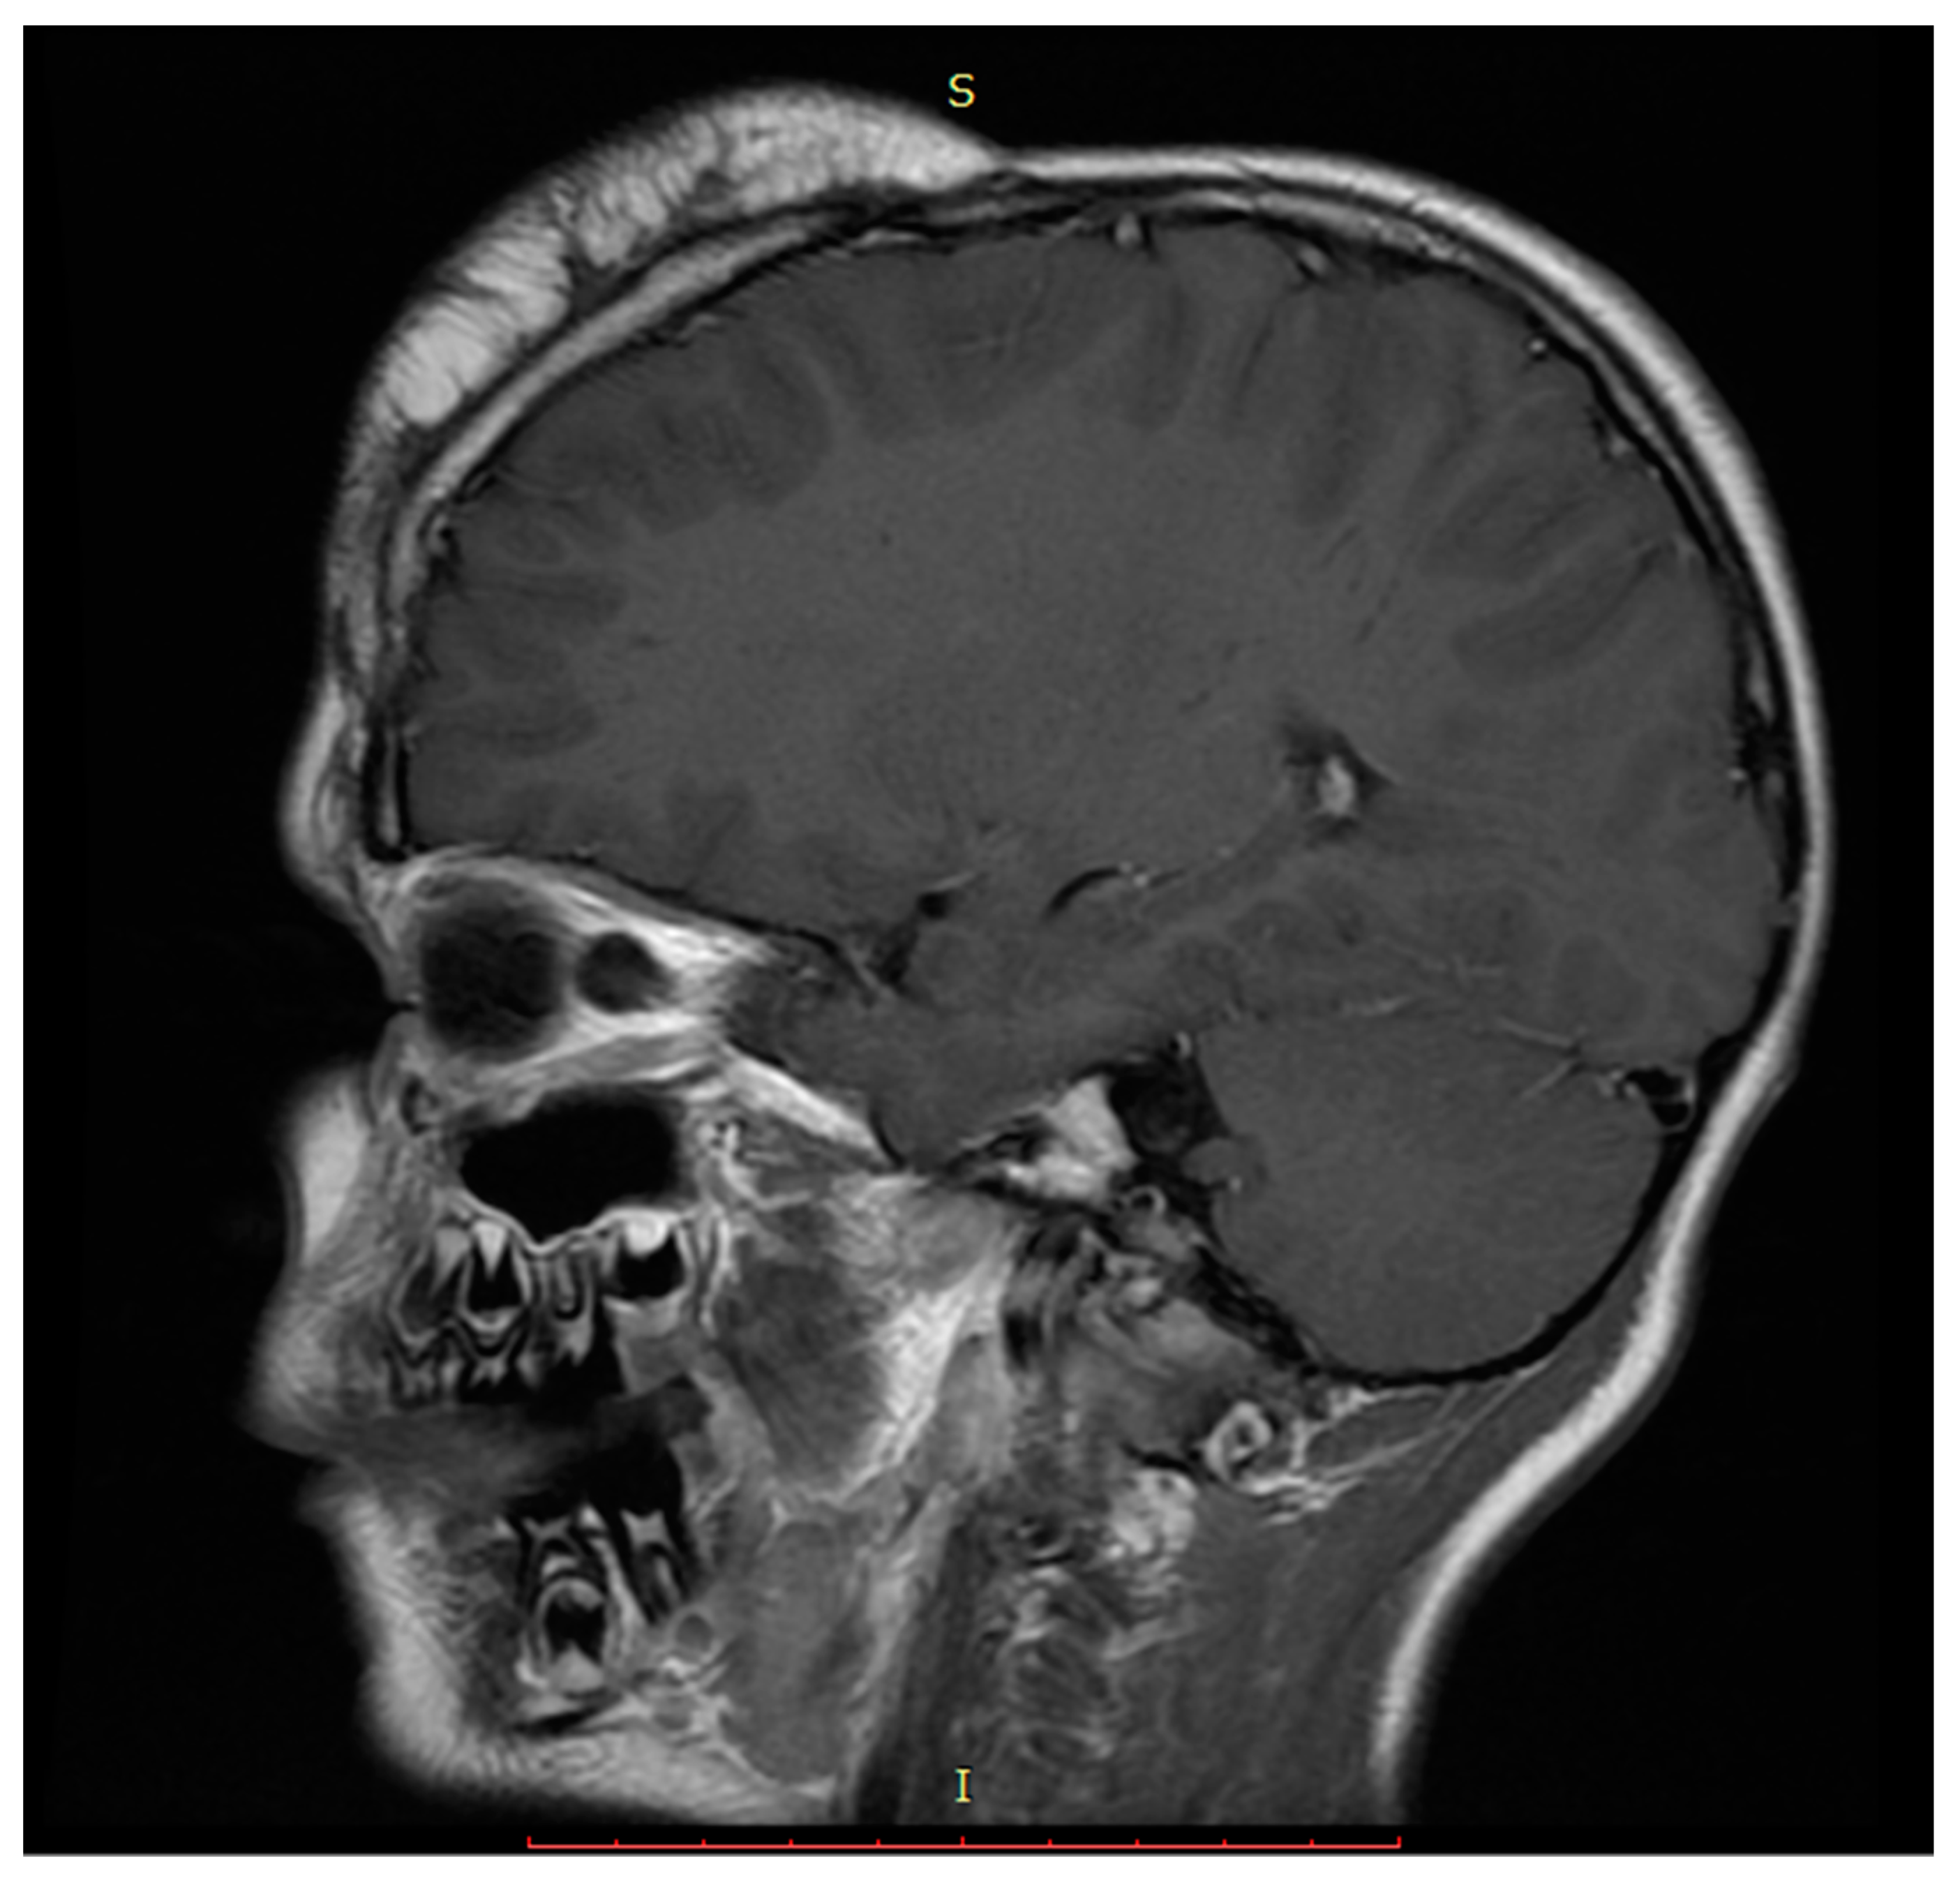

2. Case Presentation